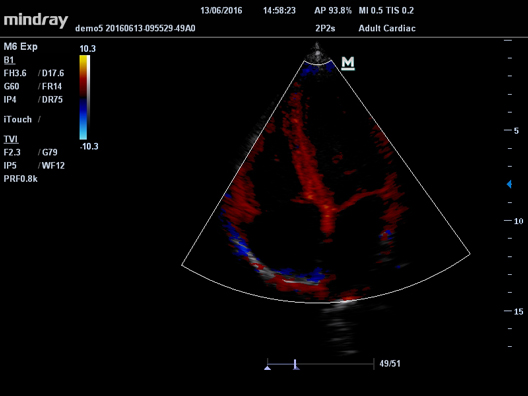

УЗ-сканер Mindray М6 exp представляет собой полнофункциональную портативную, размером с ноутбук, систему цветной допплерографии. Аппарат обеспечивает безупречную визуализацию в формате 2D. Оснащенная специализированными технологиями система М6 exp является оптимальным вариантом для применения.

HR Flow

Передовая технология на основе эксклюзивного алгоритма обработки изображений Mindray, обеспечивающая улучшенную визуализацию мельчайших сосудов и сложных структур потока.